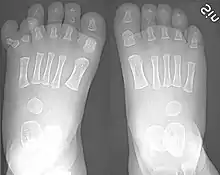

Right-sided duplication of the right little toe in an 8.5 months old male, with two toes (fifth and sixth) apparently forming joints with the fifth metatarsal bone, which is mildly broadened distally. The duplicated toes have almost normal growth. The fifth toe has mild varus angulation, and the sixth toe has substantial valgus angulation.

X-ray of type III central polydactyly. The middle fingers are the same length.

Classification is performed by using x-ray imaging to see the bone structures.[19]